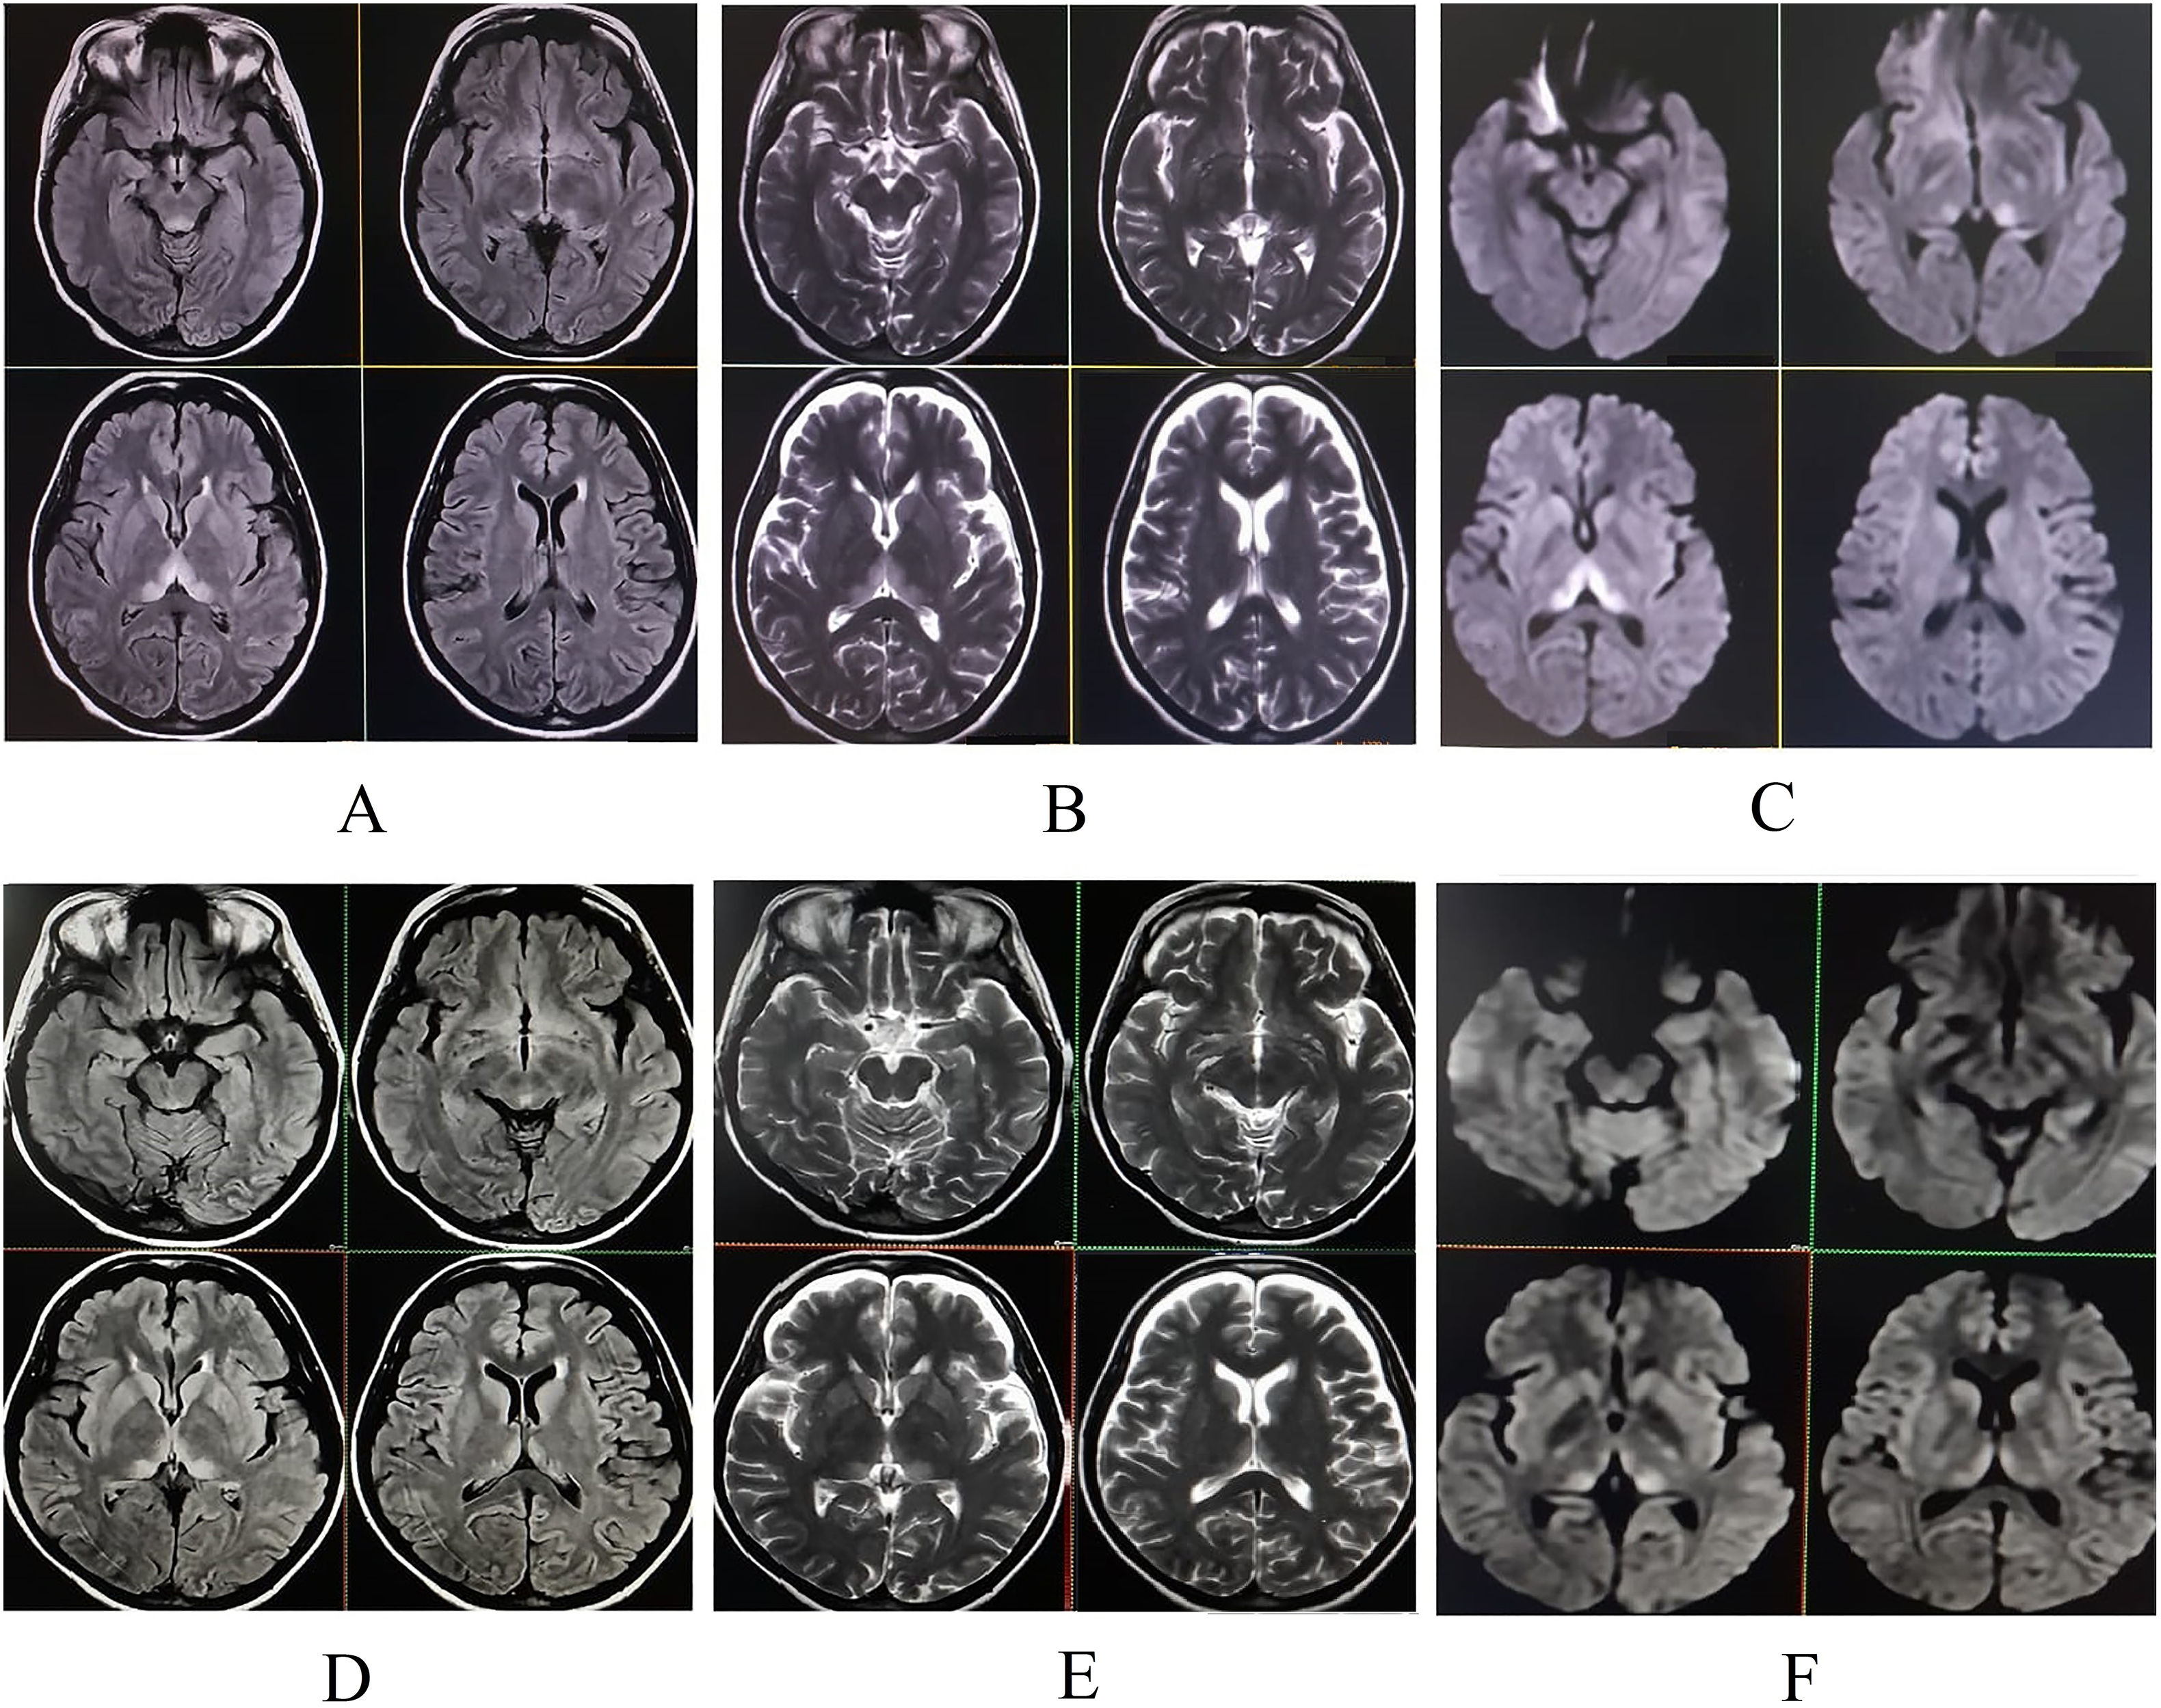

Magnetic resonance imaging (MRI) of the brain revealed symmetric hyperintensities in the thalami, hypothalamus, periaqueductal gray matter, and floor of the fourth ventricle on T2-FLAIR, T2-weighted, and diffusion-weighted sequences—findings typical of WE. Additionally, a focal hyperintensity was noted in the right superior frontal gyrus (Fig. 2), suggestive of cortical involvement—a feature more commonly associated with non-alcohol-related WE.11

She was discharged in a hemodynamically stable condition with a prescription for oral thiamine 300 mg daily. At her two-week follow-up, she had fully recovered, with no residual neurological deficits. Repeat brain MRI showed resolving changes with hyperintensity in the right superior frontal gyrus on T2-weighted images (Fig. 1).

Upper panel (pre-treatment): Initial MRI of the brain. T2-FLAIR (A), T2-weighted (B), and diffusion-weighted imaging (C) sequences demonstrate hyperintensities in the periaqueductal region, mesencephalic tectum, hypothalamus, and paraventricular and medial thalami, consistent with Wernicke's encephalopathy.

Lower panel (post-treatment, two-week follow-up): Corresponding T2-FLAIR (D), T2-weighted (E), and diffusion-weighted imaging (F) sequences show significant resolution of the previously noted lesions following thiamine therapy.